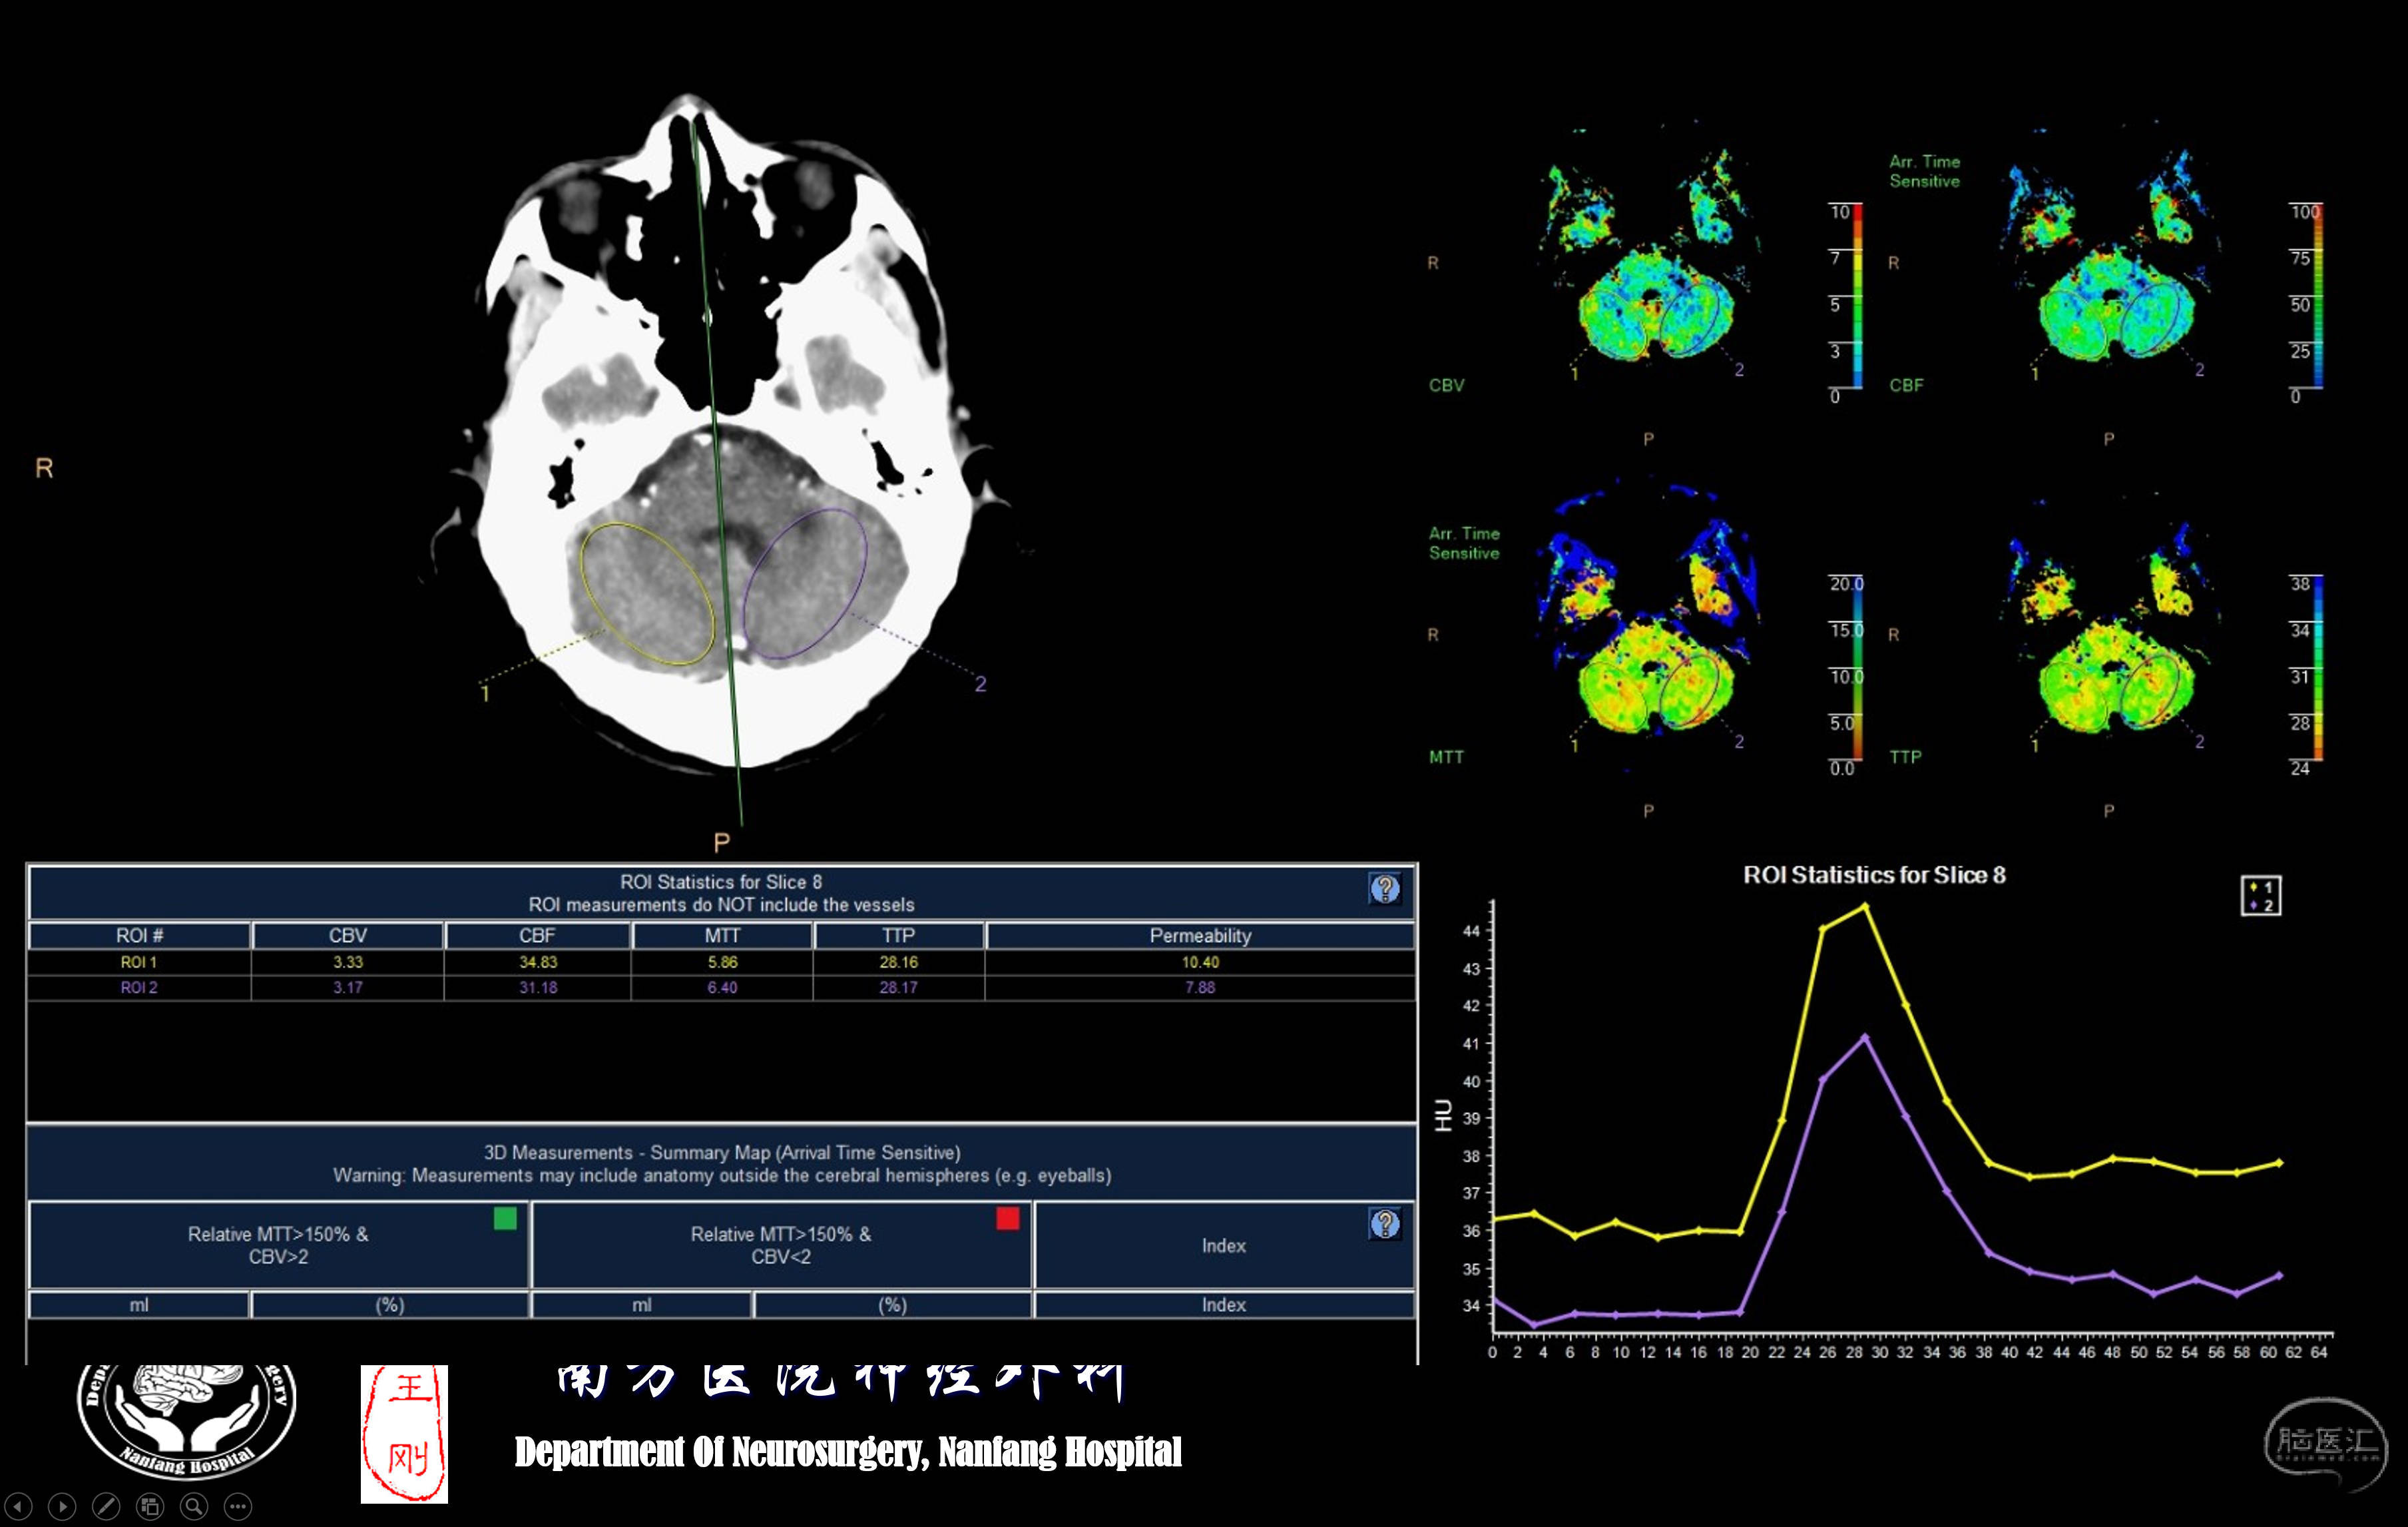

灌注CT提示后循环低灌注。患者头晕症状明显,手术意愿强烈,同时由于先前介入开通不成功的影响,排斥包括复合手术在内的介入治疗。在了解了枕动脉-椎动脉搭桥不需要开颅后,当即同意!